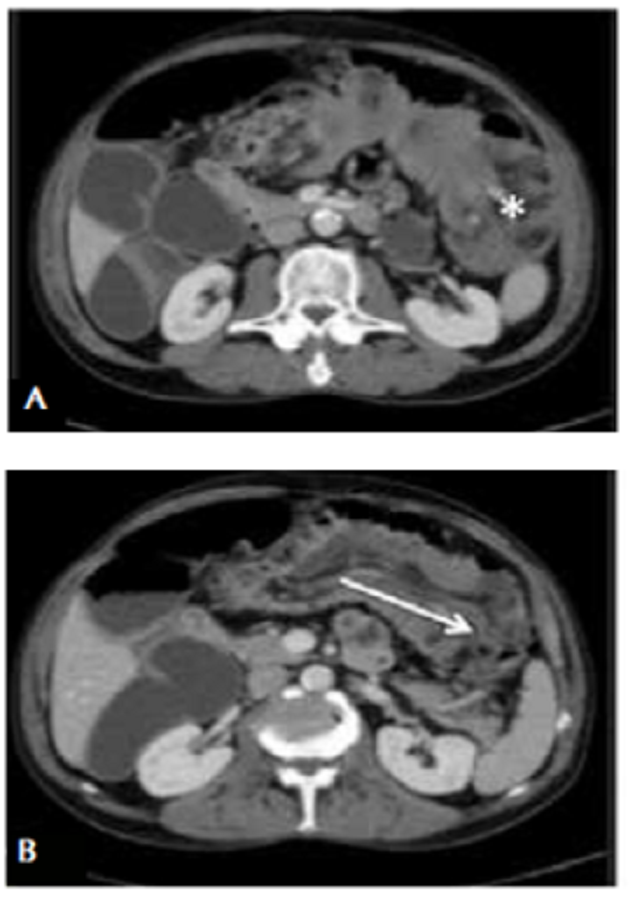

En el examen físico, el abdomen estaba ligeramente distendido, sin signos de irritación peritoneal. En el mesogastrio, se palpaba una masa de 4 x 7 cm de diámetro. Los exámenes de laboratorio no presentaron anormalidades. En la radiografía abdominal se observaron signos de obstrucción intestinal con asas dilatadas de intestino delgado. En la TC abdominal se encontró un patrón obstructivo con niveles hidroaéreos e importante dilatación de las asas del intestino delgado, que se relacionó con una intususcepción del colon transverso en el colon descendente (colocólica) (figura 1).

La TC es la modalidad de imagen de elección para el diagnóstico de intususcepción en los adultos. En esta técnica, se presenta como una masa en forma de salchicha en el corte longitudinal y como una masa en diana en el corte transversal, por el efecto de la pared intestinal y el mesenterio dentro de la luz, tal como se presenta en el segundo caso 23. Su rango de precisión diagnóstica es del 58 % al 100 % 24,25. Autores como Azar y Berger informan que la TC abdominal diagnostica con precisión la intususcepción intestinal en 78 % de los pacientes 1.